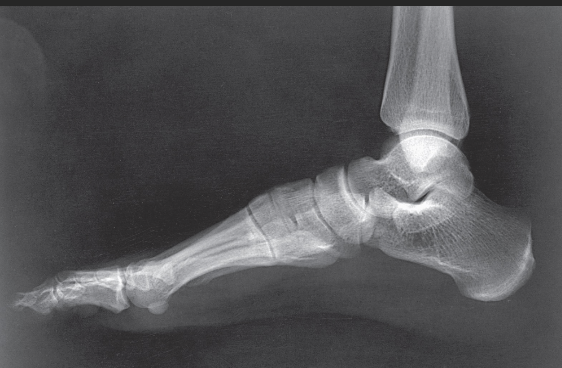

Name this projection.

Lateral calcaneus

What type of projection is it?

Mediolateral

Is the patient on the affected or unaffected side?

Affected

State specifically where the CR enters.

Perpendicular to the calcaneus // 1" distal to the medial malleolus

Which tarsal is in profile?

Calcaneus

Which radiographically significant landmark is open?

Sinus tarsi